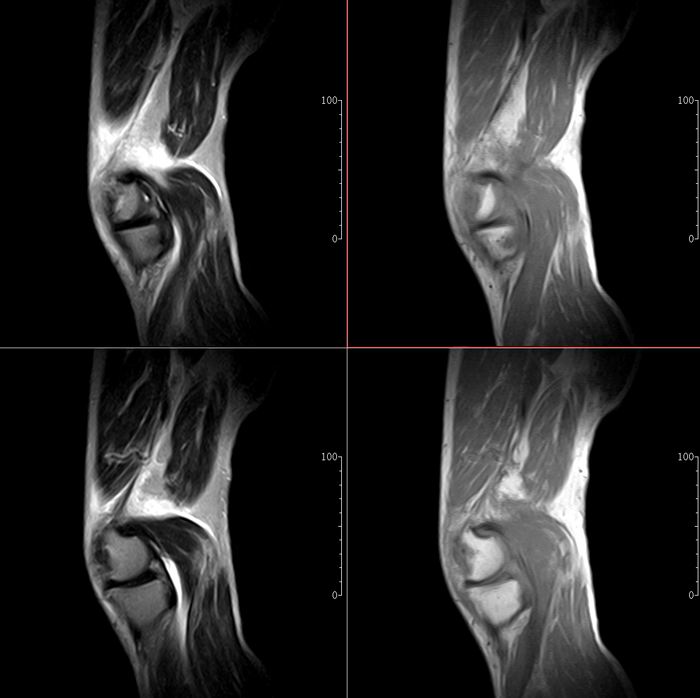

标题: MRI1910:M 687Y。近日因外伤疼痛,而就诊。

m 687y。近日因外伤疼痛,而就诊。有外侧副韧带损伤吗??因片子较差各位请包涵。

这算什么位置呢?矢状位?冠状位?

关节退行性变伴股骨外髁关节面下囊肿,不除外剥脱性骨软骨炎.关节积液,髌骨软化症

体位不标准。关节退变伴关节积液。

1)膝关节骨质退行性改变。

2)由于体位的关系不能确定有外侧副韧带的损伤。

关节退变伴关节积液,外侧副韧带的损伤

关节积液,外侧副韧带的损伤